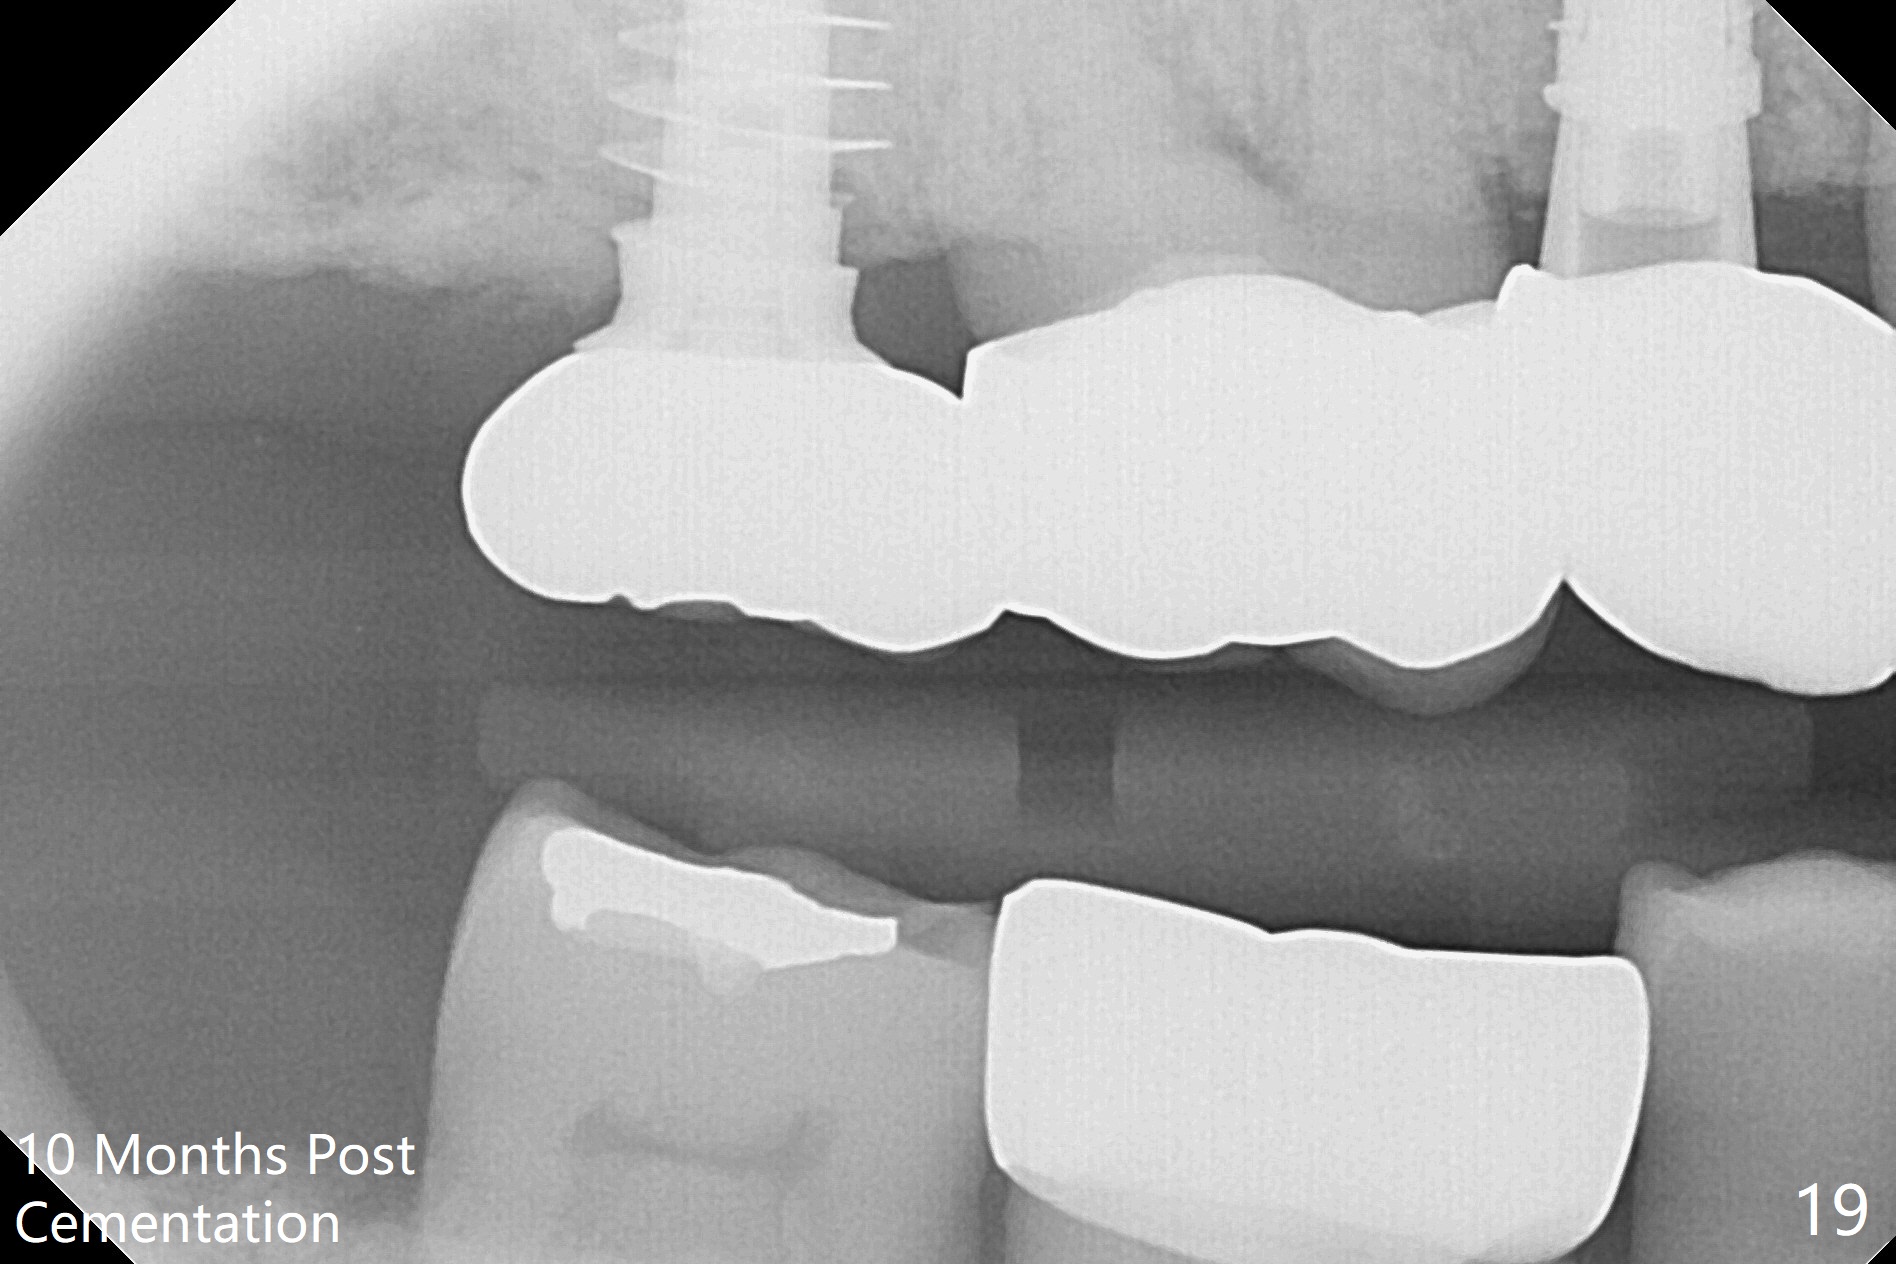

Preop exam shows posterior occlusal collapse (Fig.1) with #3 lost crown and #4 residual root. There is no ridge atrophy at #2 buccopalatally (Fig.2). The root stump of the tooth #4 is oblong, apparently consisting of 2 roots (Fig.3). There is a pointed septum at #4 socket (Fig.4, severe palatal wear of the anterior teeth (^)). After the septum is flattened with surgical handpiece and #8 round bur, 1.6 mm drill is used to start osteotomy in the septum, followed by Magic Drills (MD) and Magic Expanders (ME) alternatively. Osteotomy at #2 is initiated with Magic split, followed by MD and ME in the same manner. Dummy implants are tried in (Fig.5). Because of limited vertical height, Magicore (5.5x9(1) mm) is placed at #2, while a 4x13 mm FC implant 1-2 mm deeper than usual at #4 (Fig.6, ~ 55 Ncm). When a 5x4(2) mm pair abutment is placed at #4, there is no clearance between the Magicore at #2 and the abutment and the opposing dentition. A splinted provisional is fabricated at #3 and 4 to increase the posterior vertical height (Fig.7 P,8). In fact the occlusal contact is confined to the portion of the provisional at #3. The provisional has to extend to #4 to keep bone graft (Fig.6 *) and collagen plug in place. Liquid food is recommended at least 2-3 weeks, since there is no functional occlusal contact on the left. When the wound heals at #4 approximately 2-3 weeks, the splinted provisional can be sectioned with removal the portion at #4 to reduce micro-movement. By the evening the patient is doing well without nasal hemorrhage (sinus lift at #2 (Fig.6 *) or TMJ disturbance (due to increased vertical height).

The right posterior final restorations (Fig.14) are fabricated as planned: increase in vertical height (Fig.15). The increase is minimal (Fig.14, 17(#2 limited crown height), 16 (#2 crown being thin *)). Fig.17,18 are taken immediately post cementation. There is no bone loss 10 months post cementation (Fig.19,20). The gingiva is healthy around the implant crowns (#2, 4 and 28) 1 year 4 months post cementation (Fig.21,22).